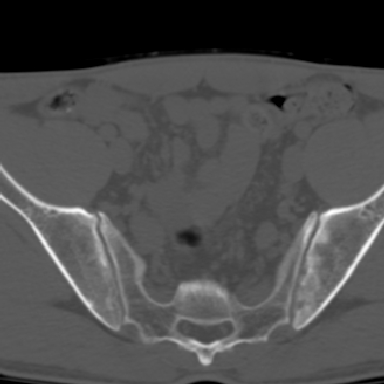

m 30 腰背部不适半年; 清晨时僵硬; 活动症状有所改善

双侧骶髂关节下2/3关节面模糊,毛糙,可见小囊状骨质破坏区.支持强直性脊柱炎.

强直性脊柱炎的早期改变!不仅表现为双侧骶髂关节,第5腰椎与骶椎间的关节突关节也有类似改变。

双侧骶髂关节下2/3关节面模糊,毛糙,髂骨侧可见小囊状骨质破坏区,骶髂关节间隙增宽(软骨破坏期)。支持早期强直性脊柱炎。

双侧骶髂关节下2/3关节面模糊、毛糙,可见小囊状骨质破坏区,呈虫咬状改变,周围可见增生硬化.支持强直性脊柱炎早期表现.

双侧骶髂关节髂骨面硬化,毛糙,小囊变,属于早期强直性脊柱炎